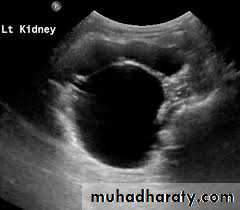

Ultrasonography; is the standard method for identifying hydronephrosis in infancy. Postnatal ultrasound imaging is usually deferred until day 3 of life, to allow for improvement in the relative oliguria, which could lead to underestimation of the degree of hydronephrosis.DIAGNOSIS